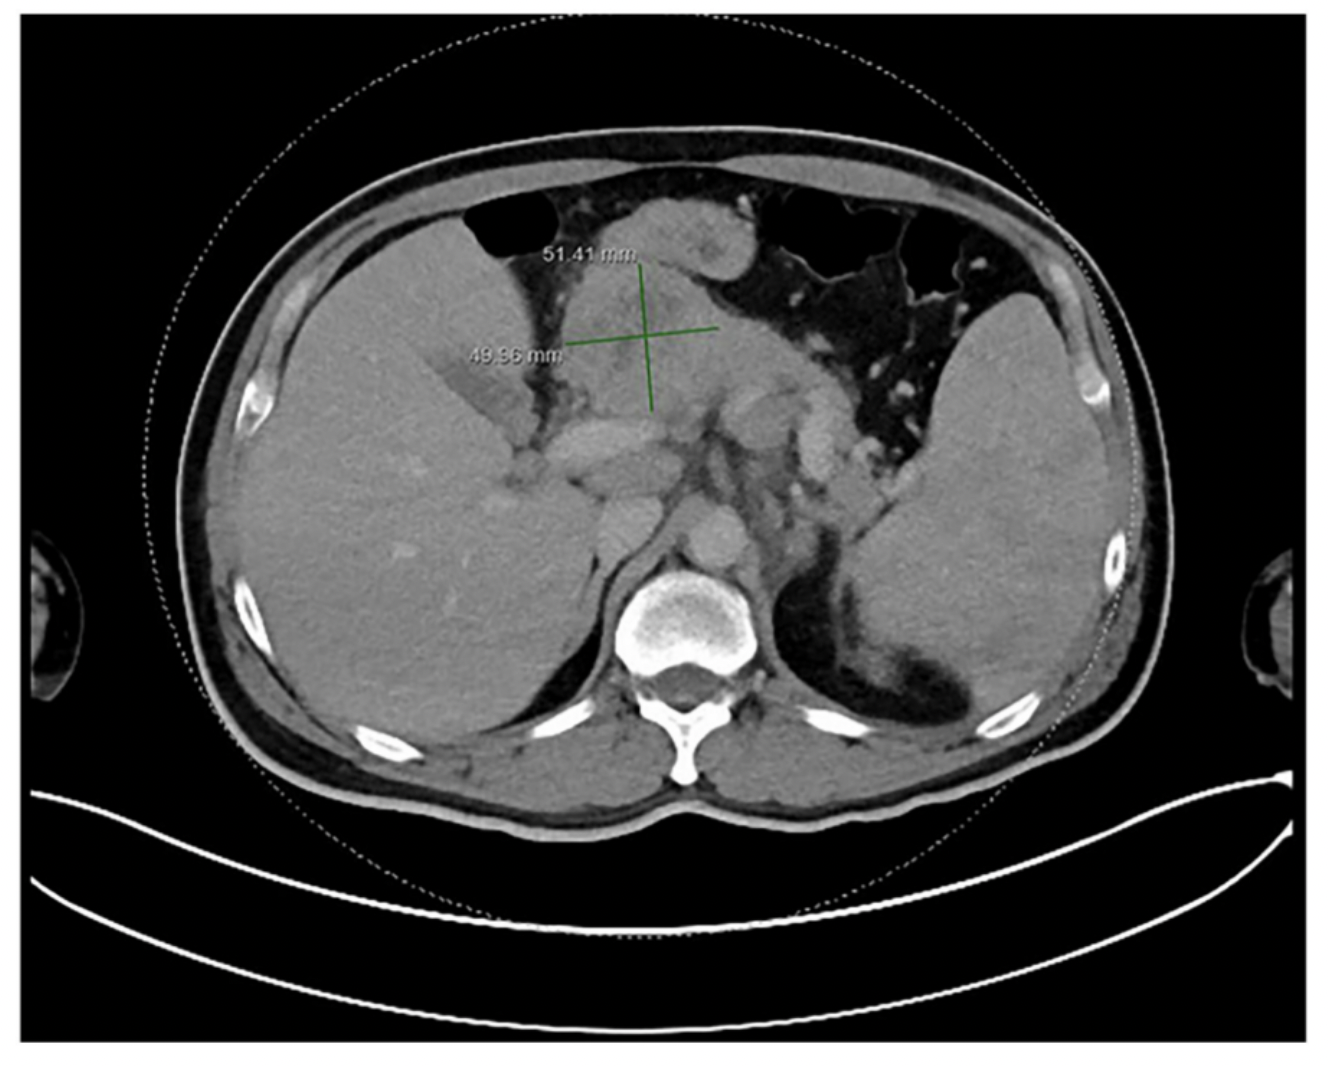

Rare Sciatic Nerve Tumor in Child Successfully Treated with Microsurgery

“This case underscores the importance of meticulous surgical technique, the potential value of IONM, and vigilant postoperative care in achieving optimal outcomes for deep-seated pediatric neurofibromas.” BUFFALO, NY — January 21, 2026 — A new case report was published in…